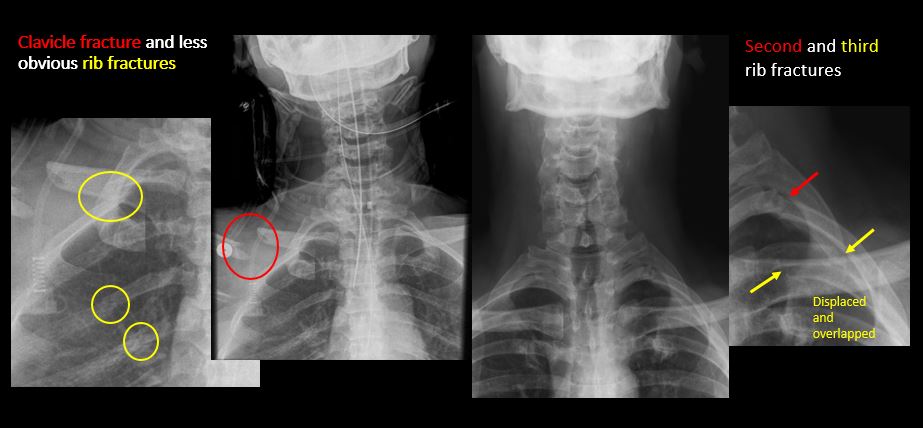

The included maxillofacial region, thoracic spine, ribs, or other bones of the upper thorax are abnormal. |

No | NA |

There is air or a foreign body or other abnormality in the soft tissues of the lower head, neck or upper thorax. |

Yes | NA |